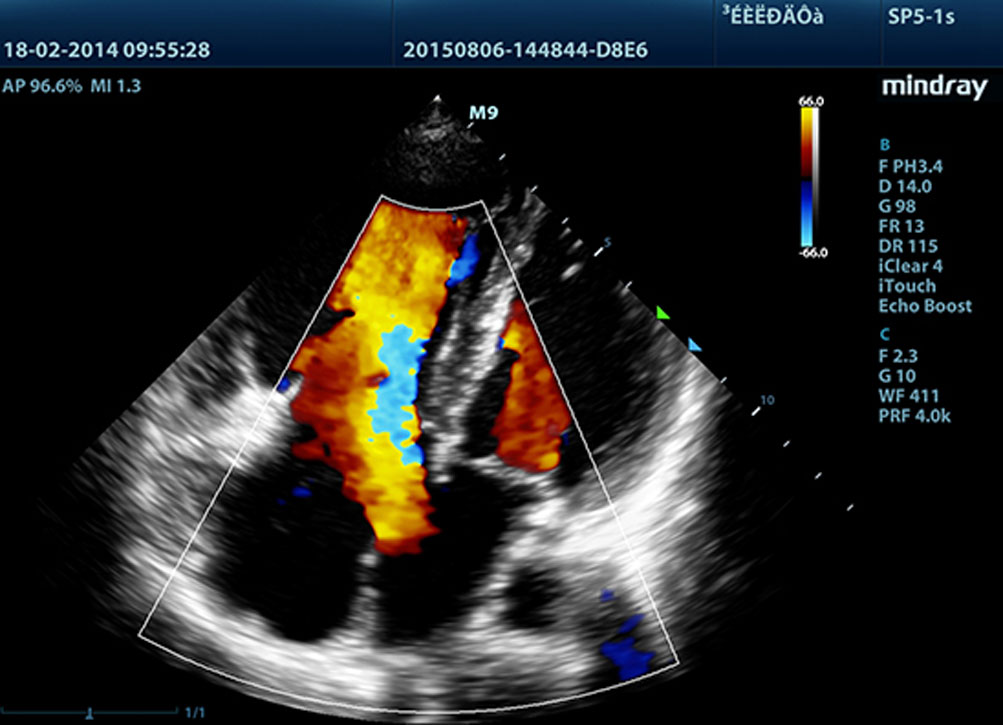

Technologie dostarczaj?ce ostrzejsze obrazy - wszystkie sondy kompatybilne z M9 s? wyposa?one w unikaln? technologi? 3T Firmy Mindray. Dodatkowo technologia Single Crystal (pojedynczego kryszta?u), oferuje lepsz? penetracj? i dynamiczny obraz przep?ywu w trybie Dopplera Kolorowego, zw?aszcza podczas skanowania trudnych przypadkÃģw.

Echo Boost?

Unikalna technologia adaptacyjnego przetwarzania sygna?u Firmy Mindray z inteligentnym wykrywaniem echa, zaprojektowana do wykorzystywania informacji o stosunku ?sygna? / szumâ w celu wzmocnienia s?abych sygna?Ãģw echa, przy jednoczesnym t?umieniu zak?ÃģceÅ, zapewnia bardziej zrÃģwnowa?on? jasno?? obrazu i lepsz? wizualizacj? warstw tkanki mi??nia sercowego.